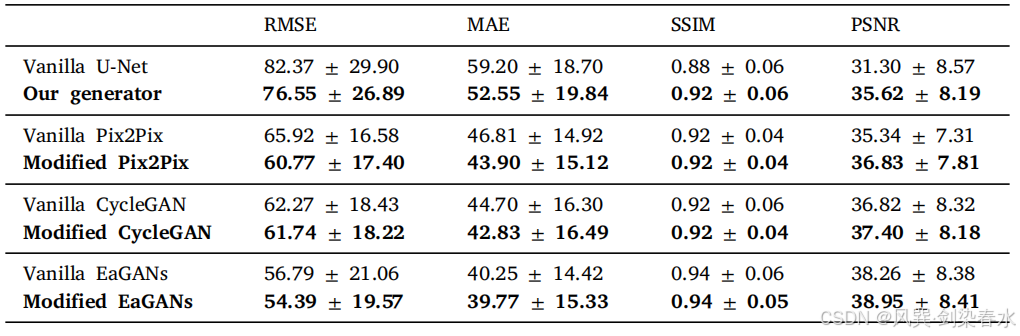

Table 4 | 对所提出的生成器进行了消融研究,其中,Vanilla 指的是原始模型,而 modified 则是指使用开发的生成器替换原有的生成器:

Table 5 | 与各种改良模型的比较,用于消融研究: